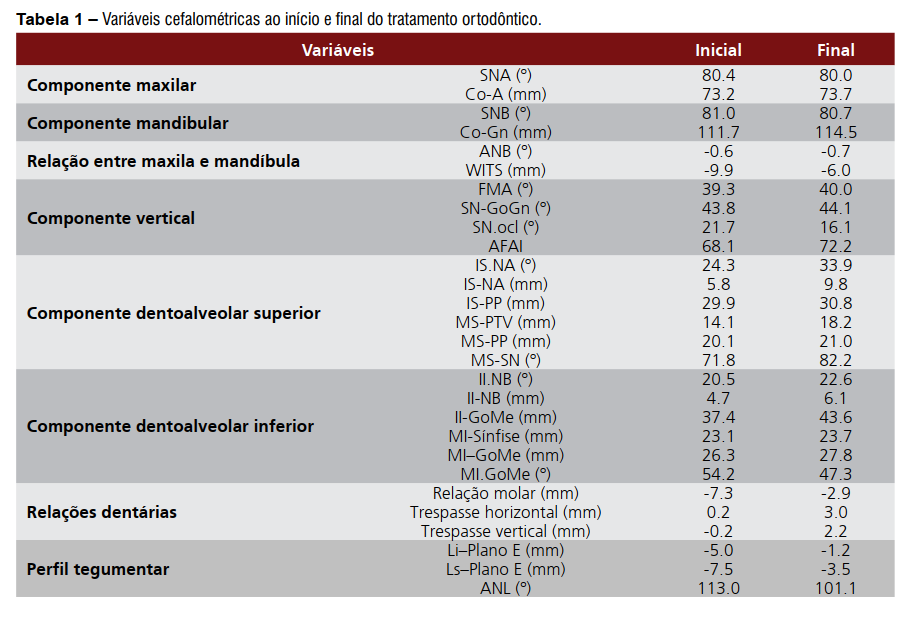

O componente esquelético da maxila não apresentou grandes alterações, entretanto, a mandíbula teve significante crescimento representado pela variável CoGn. Também houve suave aumento das variáveis que representam o padrão da face no sentido vertical, com destaque para a alteração sofrida pela variável AFAI, que teve aumento de 4,1 mm (Tabela 1).

O componente dentoalveolar da maxila apresentou maiores alterações, assim como já era esperado. Os incisivos superiores apresentaram vestibularização e protrusão enquanto os molares superiores apresentaram mesialização com angulação da sua coroa para a mesial (Tabela 1). O componente dentoalveolar inferior apresentou suaves alterações, principalmente em relação à extrusão sofrida pelos incisivos inferiores (Tabela 1).

Na relação entre os dentes superiores e inferiores houve grande melhora representada pelas variáveis:

relação molar, trespasse horizontal e trespasse vertical (Tabela 1), assim como houve visível melhora em relação ao perfil facial, que ao final do tratamento se apresentava menos côncavo (Tabela 1)

Os efeitos dessa mecânica em duas fases, quando comparado à mecânica ortodôntica realizada em uma fase somente, estão baseados no fato de que o avanço da maxila pelo uso da máscara de Petit promove a melhora no posicionamento dos incisivos, principalmente no arco superior, o que pode ser verificado quando se observa a protrusão e inclinação para vestibular dos incisivos superiores e a mesialização e angulação mesial sofrida pelos molares superiores por meio da mecânica ortodôntica realizada pela protração da maxila¹³⁻²² (Tabela 1). Além disso, outro fator que reforça a escolha desta mecânica em duas fases é que a utilização da protração maxilar no tratamento de má oclusão de Classe III tem alcançado merecido destaque na última década, muito em decorrência dos resultados favoráveis e em um período relativamente curto de tratamento (4 a 9 meses de fase ortopédica)3,15.

No caso apresentado nesse trabalho, as alterações esqueléticas ocorreram em menor proporção quando comparadas às alterações dentoalveolares (Tabela 1). Entretanto, estima-se que a associação dessas alterações favorece a correção da discrepância anteroposterior, assim como a harmonia da face e consequente estética do sorriso. A aplicação do protocolo em duas fases em uma paciente pós-pico de crescimento pode gerar efeitos esqueléticos no sentido de minimizar a discrepância anteroposterior existente ao início do tratamento, principalmente se o tratamento se iniciar no início ou logo após o surto de crescimento pubera¹³.

O aumento da altura facial anterior inferior (AFAI) é outro efeito da mecânica aplicada ao tratamento e que colabora para atratividade da face. Os registros cefalométricos inicial e final do paciente mostram para um aumento de 4,1 mm (Tabela 1) da AFAI durante o tratamento. O aumento da AFAI promove uma rotação da mandíbula no sentido horário, diminuindo a projeção do mento e favorecendo a estética da face para o paciente Classe III esquelética¹¹ (Figura 11). Apesar dos